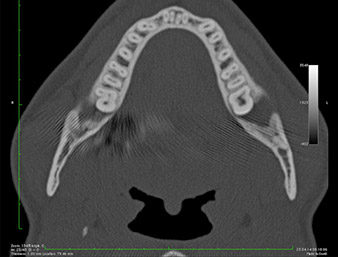

It could be seen in the 3D image (digital volume tomography) that the root remnant was located disto-caudally in the transition from the horizontal to the ascending portion of the mandible (Fig. 2).

DVT-image

Fig. 2: Transverse DVT image of the root remnant in the retromolar region.

Based on his medical history, our patient (non-smoker, 26 years old) had a very good chance of a successful outcome. Due to indication of the root remnant’s close proximity to the inferior alveolar nerve on the OPG, digital volume tomography was used in addition (6).

The very close proximity discovered made it necessary to perform a precise and atraumatic osteotomy. In this case, clinical observations and comparative studies favour piezo surgery which has been available since the end of the 1990s (9-11). Due to the characteristic micro-oscillation of these systems, it is possible to remove bone selectively, thus enabling minimally invasive preparation.